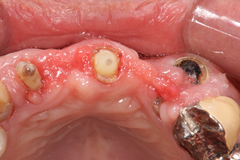

<治療後>

抜歯した部位にインプラントを埋入し半年かけて

歯肉と歯槽骨を再生させて審美的な歯(セラミック冠)を入れました。